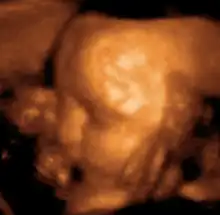

Sonogram of a fetus at 14 weeks (profile)

Head of a fetus, aged 29 weeks, in a "3D ultrasound"

The potential for ultrasonic imaging of objects, in which a 3 GHz sound wave could produce resolution comparable to an optical image, was recognized by Sergei Sokolov in 1939. Such frequencies were not possible at the time, and what technology did exist produced relatively low-contrast images with poor sensitivity.[34] Ultrasonic imaging uses frequencies of 2 megahertz and higher; the shorter wavelength allows resolution of small internal details in structures and tissues. The power density is generally less than 1 watt per square centimetre to avoid heating and cavitation effects in the object under examination.[35] Ultrasonic imaging applications include industrial nondestructive testing, quality control and medical uses.[34]

Medical ultrasound is an ultrasound-based diagnostic medical imaging technique used to visualize muscles, tendons, and many internal organs to capture their size, structure and any pathological lesions with real time tomographic images. Ultrasound has been used by radiologists and sonographers to image the human body for at least 50 years and has become a widely used diagnostic tool. The technology is relatively inexpensive and portable, especially when compared with other techniques, such as magnetic resonance imaging (MRI) and computed tomography (CT). Ultrasound is also used to visualize fetuses during routine and emergency prenatal care. Such diagnostic applications used during pregnancy are referred to as obstetric sonography. As currently applied in the medical field, properly performed ultrasound poses no known risks to the patient.[36] Sonography does not use ionizing radiation, and the power levels used for imaging are too low to cause adverse heating or pressure effects in tissue.[37][38] Although the long-term effects due to ultrasound exposure at diagnostic intensity are still unknown,[39] currently most doctors feel that the benefits to patients outweigh the risks.[40] The ALARA (As Low As Reasonably Achievable) principle has been advocated for an ultrasound examination  that is, keeping the scanning time and power settings as low as possible but consistent with diagnostic imaging  and that by that principle nonmedical uses, which by definition are not necessary, are actively discouraged.[41]